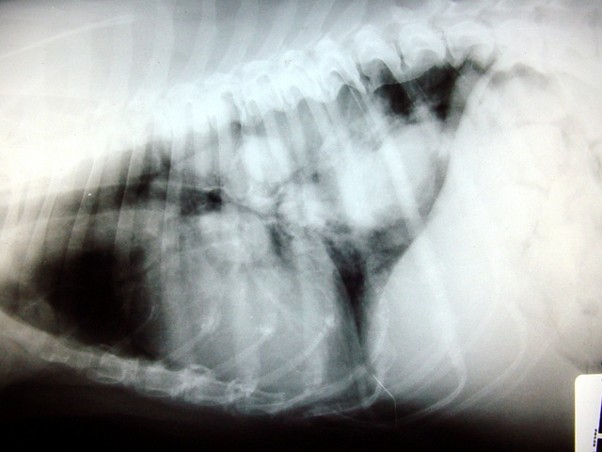

10

New cards

term image

Radiography - GDV